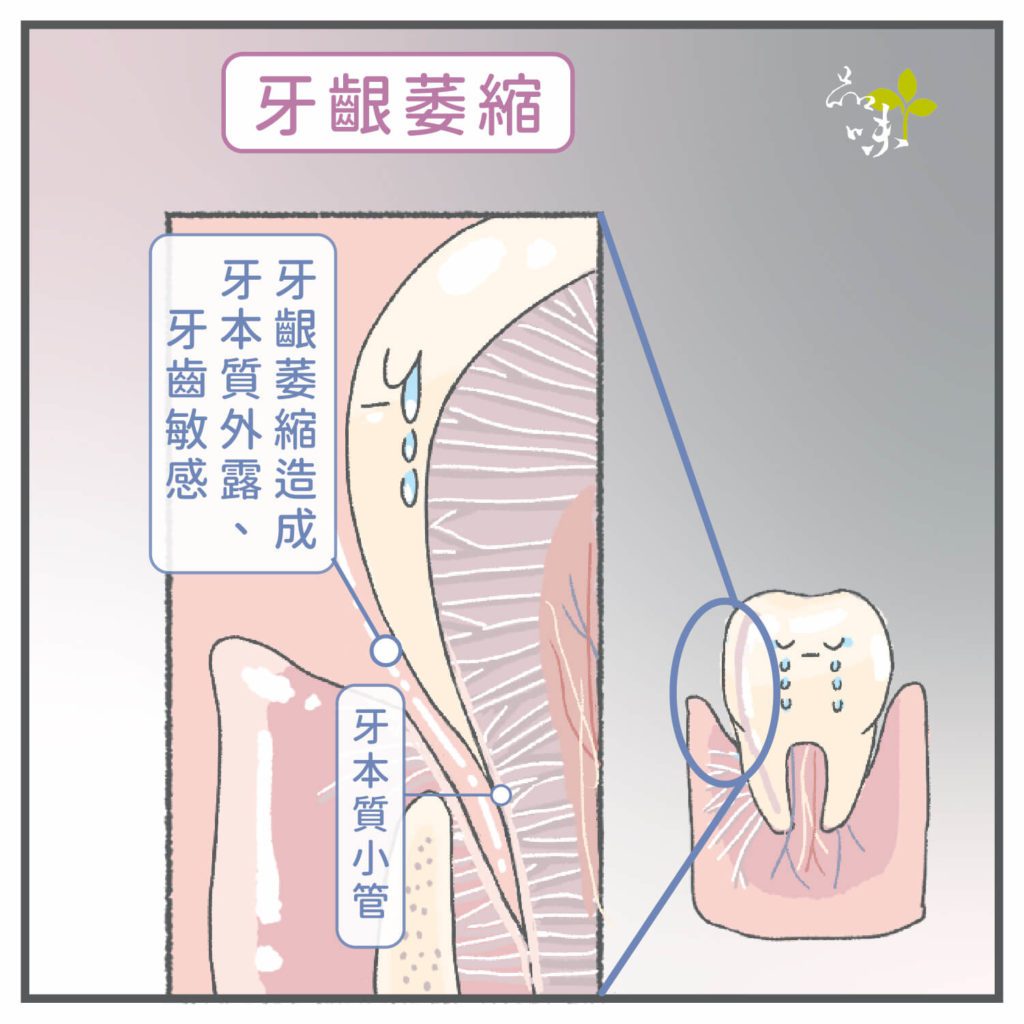

「冬天吃火鍋、夏天喝飲料,牙齒總是痠痛敏感,後來我才注意到,牙齒下方的牙肉消失了,露出黃黃的一截,以為是生病了,才趕快來掛號檢查。」你也有過類似的經驗嗎?很多人大約從20幾歲開始,就有牙齦萎縮的困擾了。這篇文章我們想跟你分享的是牙齦萎縮的成因,以及改善的方法。

某天,牙肉開始「倒退」、「減少」,讓牙根逐漸裸露出來,照鏡子一看感覺牙齒變長了──可能就是我們常講的「牙齦萎縮」現象。

這類情況下的牙齦萎縮,大部分都是因為牙刷太硬、刷牙太用力而導致。

如開始出現牙齦萎縮的情況,可以將牙刷換成軟毛的,並改正自己的刷牙方式,避免持續性對牙齦造成壓迫。